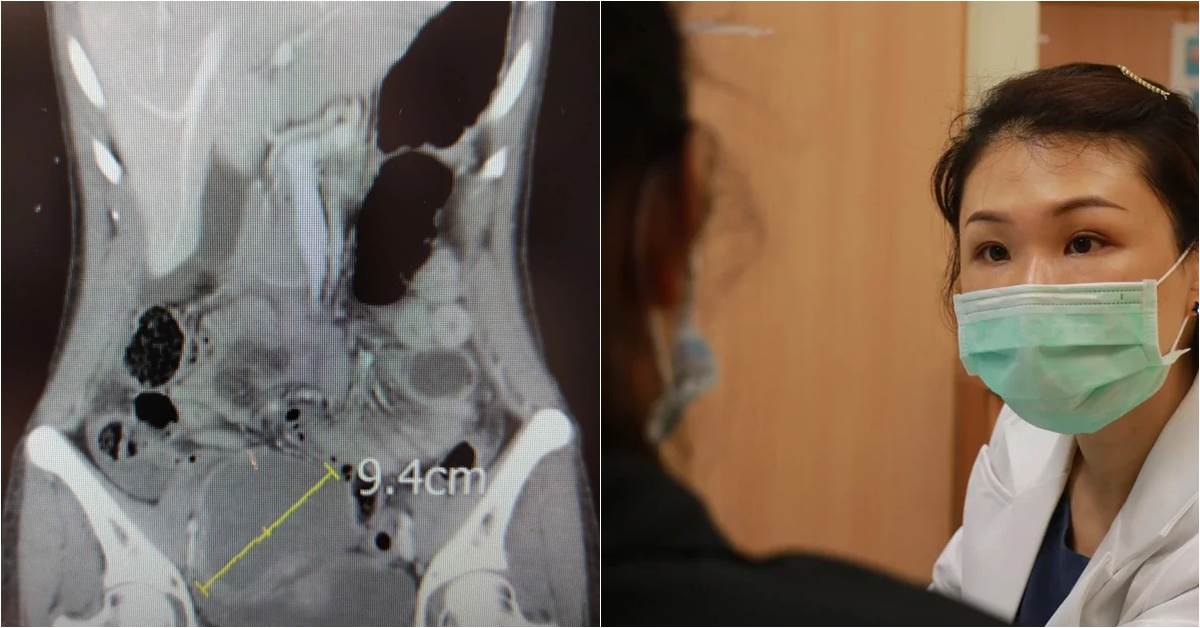

经痛别轻忽,轻熟女「苹果大」巧克力囊肿破裂挂急诊 35岁轻熟女经痛发冷不适冲到医院挂急诊,医师检查出右侧卵巢的巧克力囊肿破裂,引发急性腹膜炎,紧急手术取出如苹果大10公分的病灶。

妇产科医师从电脑断层影像发现,剧痛病因来自右侧卵巢巧克力囊肿破裂,引发急性腹膜炎,属于不能再等的急症。但苏女住院前采检确诊新冠肺炎,医疗团队全副武装在负压隔离手术室开刀,顺利用腹腔镜摘除形状有如一颗大苹果的10公分病灶。

(妇产科医师提醒,妇女经期如果疼痛感愈来愈明显、止痛药愈吃愈多、需要吃的时间愈来愈长,就建议及早就诊。)